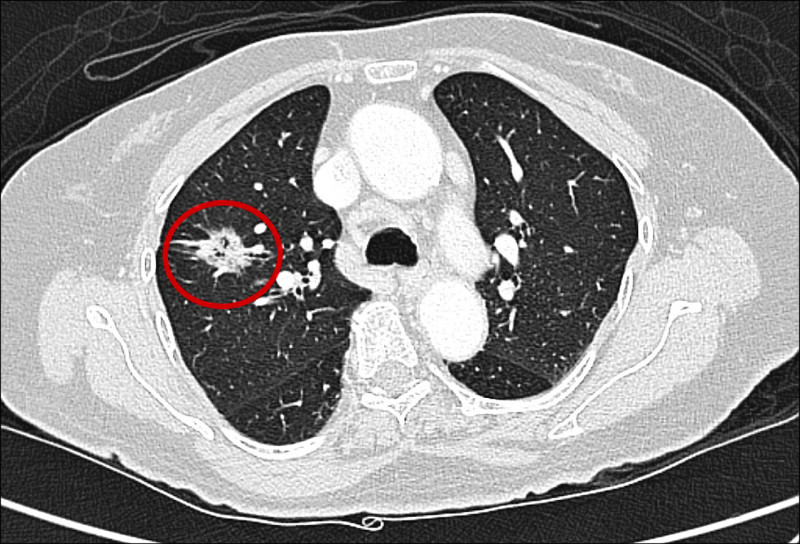

低劑量電腦斷層不只抓肺癌 台中榮總AI揪出心血管風險

女性肺癌標準化發生率首度超過大腸癌 國健署明年擬有條件補助LDCT篩檢